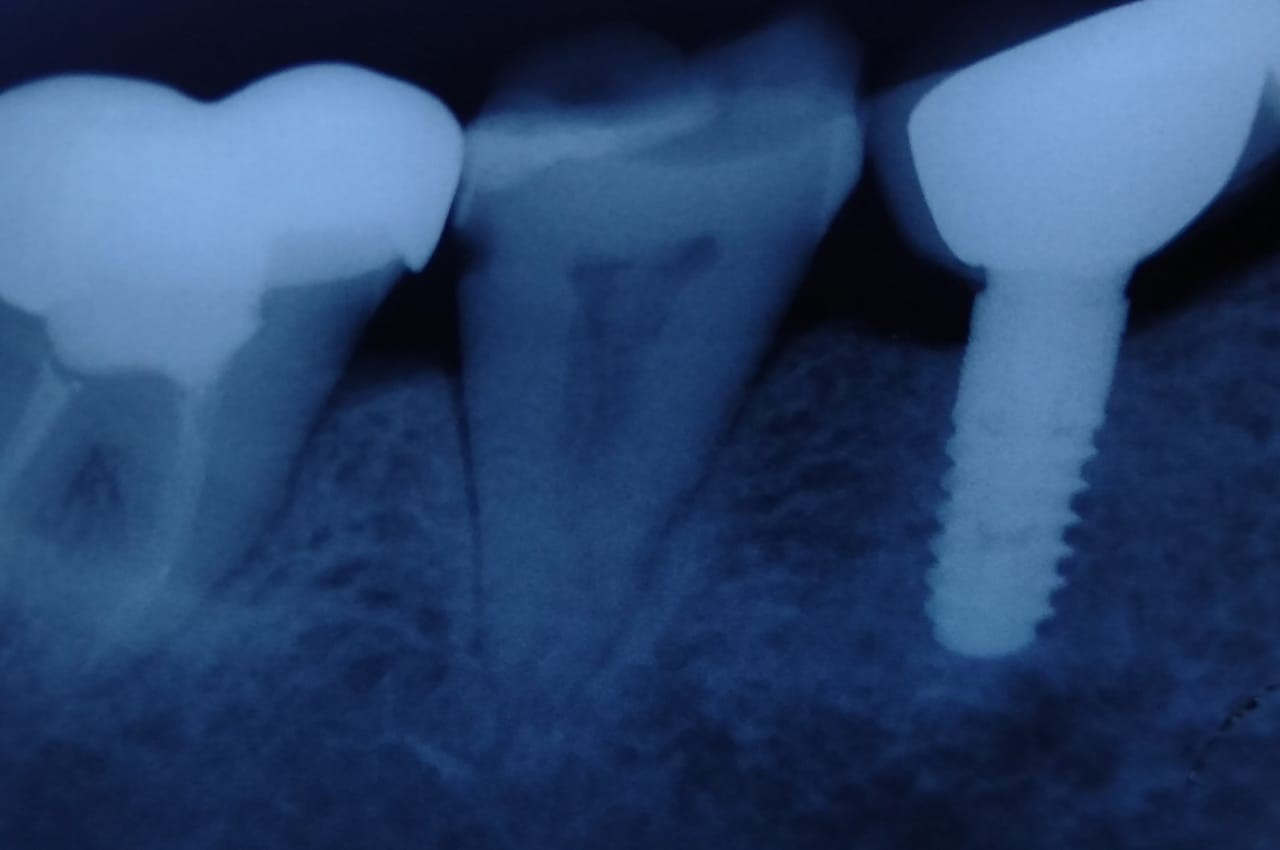

IOPA radiograph of the same

Laser assisted peri-implantitis treatment around tooth no 36.